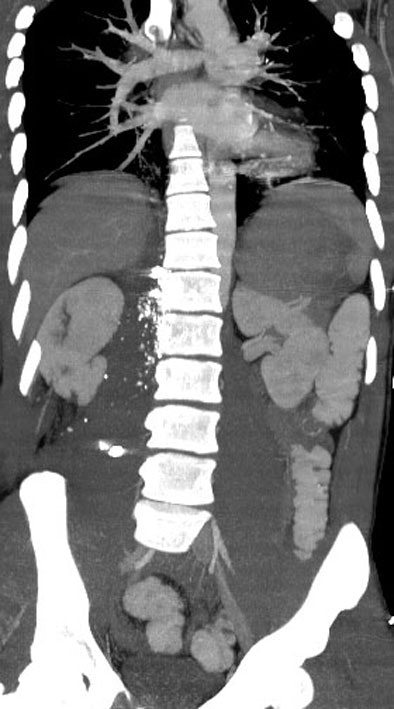

"The trajectory of the bullet can be followed if you use thick cuts on the CT scan, because it always leaves a little air path behind it that in many instance will guide you right to the injury -- so you can tell if the bullet is passed near certain structures or through certain structures," Sisley said.

![]() |

| CT shows bullet tract outlined by shrapnel on gunshot wound to the right side of the abdomen. Image courtesy of Dr. Amy Sisley. |